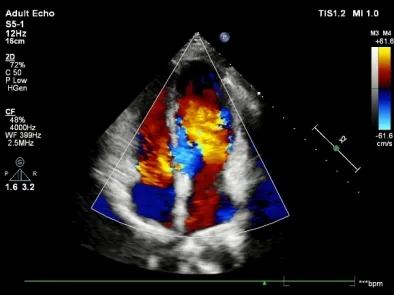

术前TTE示:膜周部室间隔缺损,基底大小11.3×10.5mm,分流口大小3.6mm,左向右分流,峰值流速4.07m/s。

释放前超声下封堵器型态良好,骑跨室间隔两侧

释放后超声

超声下可见室水平和房水平都无残余分流